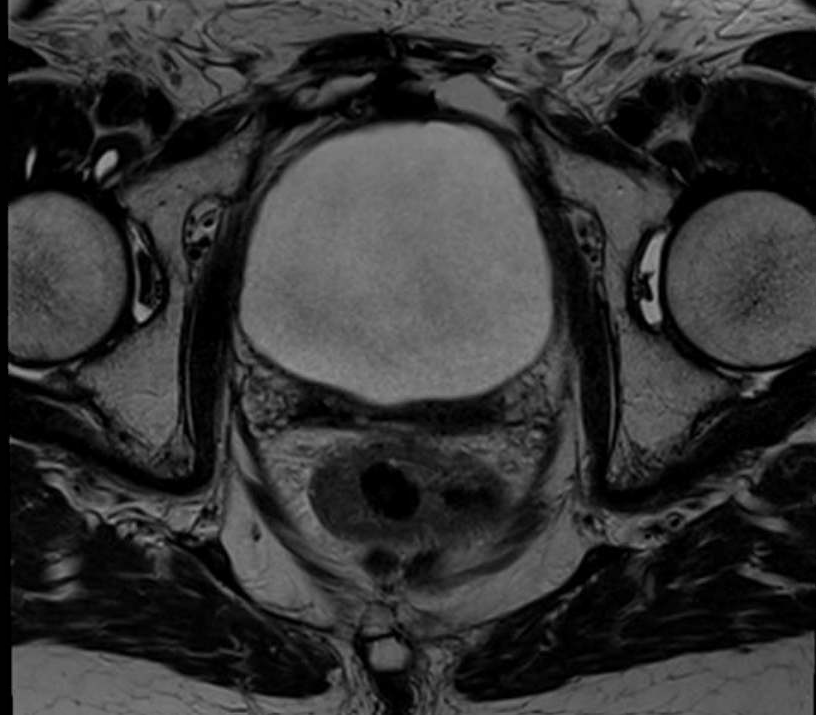

Figure 1 and figure 2 illustrate the typical interfraction movement as seen on the MRI scan. Figure 3 and figure 4 demonstrate the daily changes of the patient’s internal anatomy whilst figure 5 and figure 6 show the adaptive radiotherapy plan.

Fig 5: Radiotherapy plan

Fig 6: Plan adaptation. Tight conformality at rectal and prostate boundary is demonstrated by the arrow. Rapid reduction of high dose optimises dose delivery to the prostate and limit dose to the rectum, reducing the risk of long term toxicity.